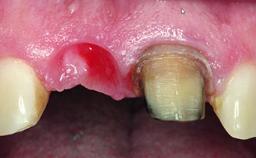

Replacement of a Failing Upper Left Central Incisor: Immediate Placement of an RC Bone Level Implant and Provisionalization

A healthy 23-year-old female patient was referred for a consultation on replacing tooth 21 with an implant-supported restoration. The patient had recently moved to the area and reported a history of endodontic and periodontal treatment for tooth 21. The tooth had been deemed non-restorable by her previous periodontist but since she was going to be moving, he recommended consulting to a dentist in her new city to continue her treatment. A review of her medical history yielded no significant findings and no known drug allergies. The analysis of her smile revealed a medium to high symmetrical smile line and a slightly discolored tooth 21.

Loading Protocol Immediate

Provisional Implant-Supported Prosthesis Prosthodontic margin < 3 mm apical to mucosal margin Prosthodontic margin < 3 mm apical to mucosal margin